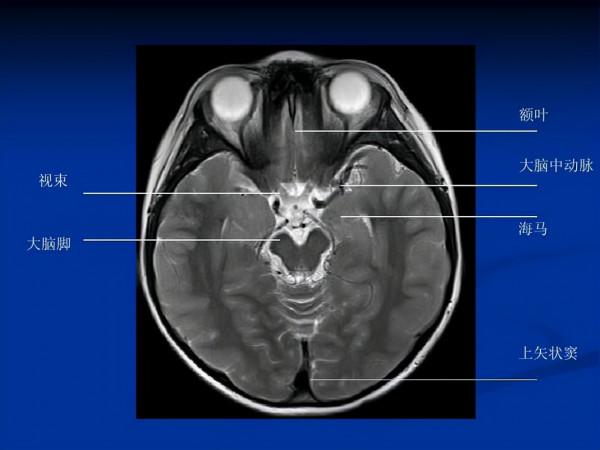

2、腦部CT

透過對腦部進行CT檢查,能夠檢查腫瘤、腦梗死等問題,但是常規檢查當中一般是不會查腦部的,因為費用比較高,所以只建議那些經常頭暈頭痛胸悶的人群,在經濟條件允許的情況下做一下腦部CT檢查,排查早期疾病。